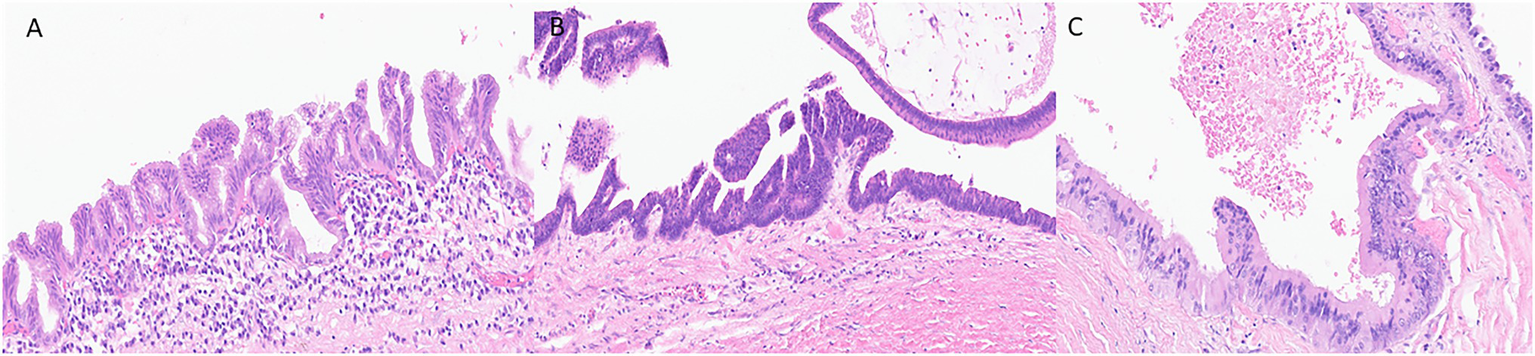

Histologically, the neoplastic epithelium of IPMNs can have various directions of differentiation. The most seen differentiations include gastric-foveolar, intestinal, and pancreatobiliary (Figure 1). However, IPMNs can display a combination of different differentiation. Gastric-foveolar differentiation is the most common type and usually occurs in BD-IPMNs. The neoplastic epithelium usually forms broader and thicker papillae and is composed of columnar epithelium with basally placed nuclei and overlying mucin caps resembling gastric-foveolar epithelium (Figure 1A). The epithelium could be flat and typically has only low-grade dysplasia (Ban et al., 2006).

Figure 1

Representative histological pictures of intraductal papillary mucinous neoplasm (IPMN). (A) IPMN with gastric-foveolar differentiation. The epithelium is flattened with basally placed nuclei and abundant mucin cap resembling gastric-foveolar epithelium. (B) An IPMN with intestinal differentiation forming villous papillae resembling villous adenoma of the colon. The cells have basophilic cytoplasm with enlarged oval and hyperchromatic nuclei and scattered goblet cells. (C) IPMN with pancreatobiliary differentiation. The neoplastic cells are cuboidal, have enlarged nuclei with amphophilic cytoplasm. (A–C) Original magnification 200×.

Intraductal papillary mucinous neoplasm with intestinal differentiation is the second most common type in which the neoplastic epithelium forms long finger-like (villous) papillae (Figure 1B). The neoplastic cells show tall-columnar cells with elongated hyperchromatic nuclei. Pseudostratification with high-grade dysplasia is often seen. All colloid carcinomas of the pancreas arise from an intestinal-type IPMN (Adsay et al., 2004; Furukawa et al., 2005).

The neoplastic epithelium forms complex, thin, and branching papillae in IPMNs with pancreatobiliary differentiation, the least common form. The cytoplasm in these cells is amphophilic, and they have enlarged nuclei and often prominent nucleoli (Figure 1C). The neoplastic cells in IPMNs with pancreatobiliary differentiation are more cuboidal (less columnar) than those seen in other IPMN differentiation types. These often have high-grade dysplasia (Adsay et al., 2002; Furukawa et al., 2005).